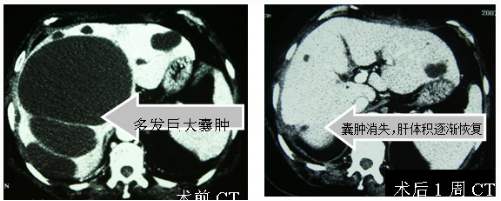

有一种遗传性的罕见疾病,叫做多囊肝。多囊肝常常合并多囊肾,这是一种常染色体显性遗传病,是可以遗传给下一代的。如果你得了这种疾病,你的后代有50%的概率患病。得了此病的患者,肝脏和肾脏可以长满大大小小,几十个甚至上百个的囊肿。

随着年龄的增大,肝脏里面的囊肿会越来越多,年龄大于60岁的时候,出现多囊肝的概率超过50%。多囊肝的患者,肝脏里面的囊肿,会压迫正常的肝脏组织,导致肝组织萎缩,患者会出现肝功能衰竭。

还有一种方法是腹腔镜微创的手术治疗,在肚皮上做几个5毫米至1厘米的小口,然后在腹腔镜下,把肝囊肿的囊壁打开,把里面的水分吸出来,这种手术方式叫做肝囊肿开窗术,是治疗肝囊肿的主要手段。

多囊肝可能需要肝移植

多囊肝的治疗方法与普通的肝囊肿不同,因为多囊肝厘米有非常多的囊肿,做手术很难全部去除,一般只能把大的囊肿去掉。平时要注意复查,监测囊肿的大小,还有肝脏功能。避免使用损害肝功能的药物,如果肝功能受损,出现肝功能衰竭,那就只能做肝移植手术了。